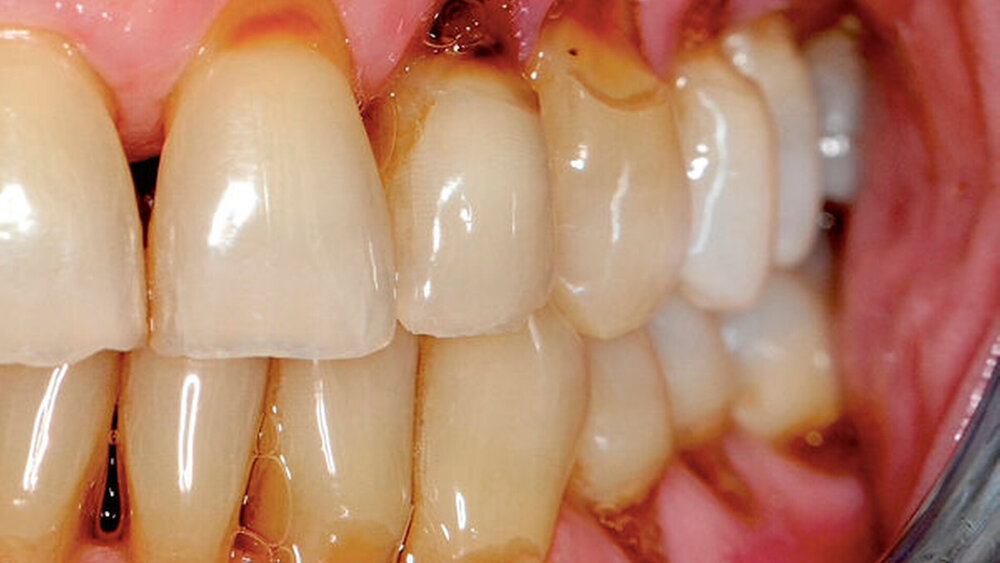

Sekundär entwickeln sich oft bakterielle, virale und mykotische Schleimhautinfektionen. Man beobachtet des Weiteren eine progrediente Zunahme kariöser Läsionen an Glattflächen, Füllungs- und Kronenrändern sowie im Bereich von Wurzeloberflächen [Jaschinski et al., 2009] (Abbildung 2a).

Beide Formen oraler Veränderungen – die mehr oder weniger stark ausgeprägten Verminderungen des Speichelflusses und die gingivalen Wucherungen – bereiten dem Zahnarzt häufig große Probleme. Als Folge der fehlenden protektiven Wirkung des Speichels können sich kariöse Läsionen – besonders im Bereich der Zahnhälse – 15-mal schneller entwickeln [Jaschinski et al., 2009]. Weiterhin können in fortgeschrittenen Fällen gingivale Wucherungen die Durchführung der Mundhygiene und die Therapie von kariösen Defekten in unmittelbarer Nähe der Gingiva erschweren. Trotz der bestehenden Schwierigkeiten sollte die vom Hausarzt, Kardiologen oder Neurologen verordnete Medikation auf keinen Fall eigenmächtig verändert oder gar abgesetzt werden. Stattdessen empfiehlt sich bei beiden Patientengruppen eine Intensivierung der Plaquekontrolle durch eine individuell abgestimmte Instruktion zur Durchführung der Mundhygiene (MHD) und in kurzen Zeitabständen durchgeführte professionelle Zahnreinigungen (Abbildung 2).